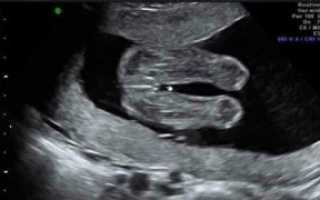

Можно ли на 16 неделе беременности узнать пол ребенка

Страстное желание узнать пол малыша на первых месяцах беременности неискоренимо. Родители высчитывают время зачатия, изучают глянцевые журналы и гадают на кофейной гуще. Родственники добавляют жару – прогнозируют девочку или мальчика и отстаивают свою точку зрения до последнего, даже если специалист четко увидел пол ребенка на обследовании.

Мы попробуем прояснить, на какой неделе (месяце) беременности результативно УЗИ, какие способы и приметы пригодятся, чтобы узнать будет ли это мальчик или девочка.

Точно ли УЗИ определит пол ребенка?

Безусловно, самым точным методом определения пола будущего любимого чада является УЗИ.

Проблема лишь в том, что УЗИ можно проводить на определенных сроках беременности, не более трех раз (на 13-й неделе, на 23-24 неделе, непосредственно перед родами).

Вывод: УЗИ – самый точный метод, но он тоже дает осечку. Срок беременности, развитие малыша, уровень специалиста, точность оборудования, положение ребенка в животике на момент проведения исследования – все эти важные факторы могут повлиять на результат.

Важно! Гениталии малыша формируются на 11-й неделе. Но в самом начале формирования пениса у мальчика это скорее небольшой бугорок, чем полноценный орган, который легко заметить.

Только к 13-й неделе он вытягивается в длину и становится более осязаемым. На раннем этапе их развитие настолько незначительно, что перепутать пол ребенка очень легко.

Специалист даже очень высокого уровня может предположить, кто родится, но гарантировать результат не сможет.

Срок беременности – важный показатель

К 19 неделе хороший специалист уже сможет на 80% быть уверенным в том, кто у мамы в животике: мальчик или девочка. Мальчика определить проще, а если вы ожидаете девчушку, то лучше обратиться к узисту уже на 24-й неделе беременности.